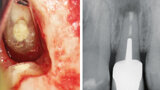

Aplikace MTA s použitím Produit Dentaires (PD) MAP System